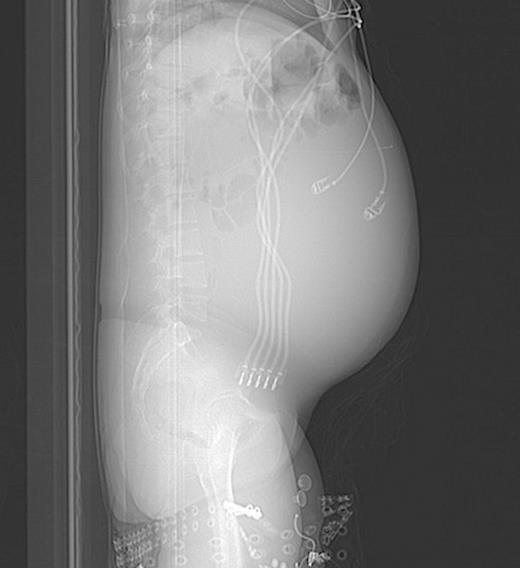

Abdominal CT, axial view, demonstrating a large fluid compartment surrounding the VP shunt catheter resulting in mass-effect, hydronephrosis, and displacement of the intra-abdominal contents

She eventually sought medical attention when she began developing diffuse, unremitting bilateral lower quadrant pain as her abdomen continued to enlarge (Fig. 1). A urine pregnancy test on admission was negative. Abdominal CT demonstrated a large fluid compartment surrounding the VP shunt catheter resulting in mass-effect, hydronephrosis, and displacement of the intra-abdominal contents (Fig. 2 and 3), establishing a diagnosis of APC.